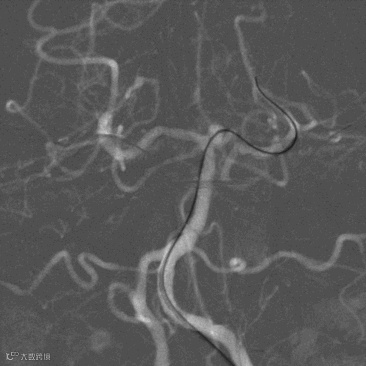

顺栓塞微导管送入QC-2.5-6-3D弹簧圈成篮,造影见动脉瘤显影浅淡,成篮理想,继续送入QC-1.5-3-Helix*2、1.5-2-Helix(图8 A,B)。

图8(A)

图8(B)

造影见动脉瘤不显影,致密栓塞,Raymond分级I级,基底动脉、大脑后动脉通畅,小心撤出栓塞微导管及支架微导管,再次多角度造影结果同前(图9 A,B),遂结束手术撤出各级导管。

图9